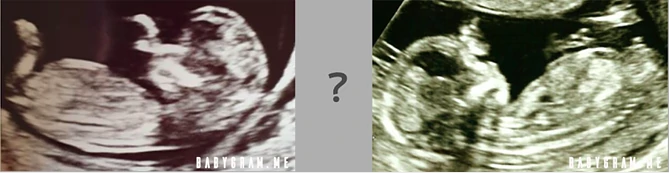

Sometimes the nub theory struggles to predict the gender of your baby. This is when the Nub shows two different angles in different positions. One picture of the baby's fetus may show a nub of a boy, whereas a picture taken from a different position may suggest it to be of a girl.

Same baby, two nubs! Yes, a girl and a boy can have a nub of the same appearance! See the examples below, which are great classics of cases that are very difficult to identify.

What's more, you cannot even see the Nub at all, or its appearance is of no particular gender, as shown in the photos below.

Boy or girl? Predicting the sex in such cases is a 50/50 game at best.